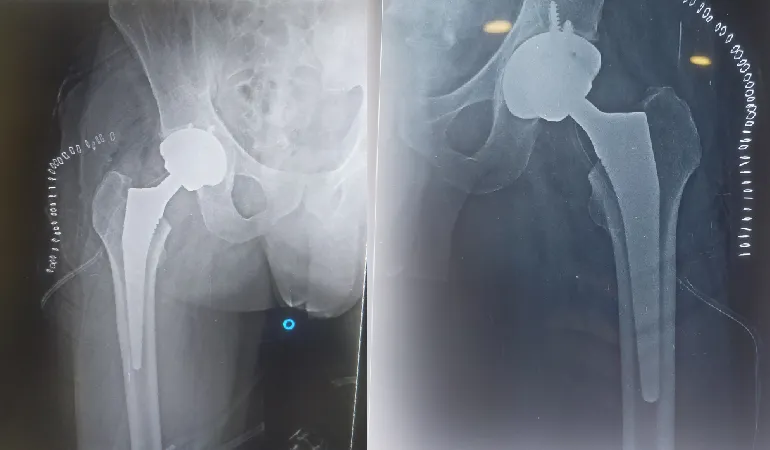

Hip Replacement Surgery, also called hip arthroplasty, is an advanced orthopedic procedure where a damaged or arthritic hip joint is replaced with a durable artificial implant (prosthesis). This surgery is recommended when chronic hip pain, stiffness, or limited function no longer improve with non-surgical treatments like medication, physiotherapy, or lifestyle modifications. At Vedant Hospital, Gota, Dr. Amish Shah offers expert hip replacement solutions for patients suffering from conditions such as osteoarthritis, rheumatoid arthritis, or hip joint injuries.

• Advanced joint damage – Imaging such as X-rays or MRI reveal significant cartilage loss or deformity.